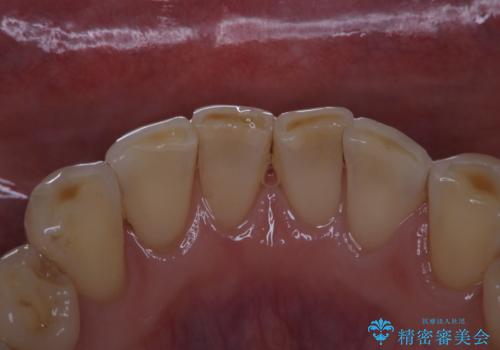

- 前歯のブリッジの治療後も定期的にPMTCを受けている方です。3カ月メンテナンスとのことでPMTC30分コースを行いました。

メンテナンスの際には、治療後のセラミックなどに問題がないかのチェックなどのも行います。